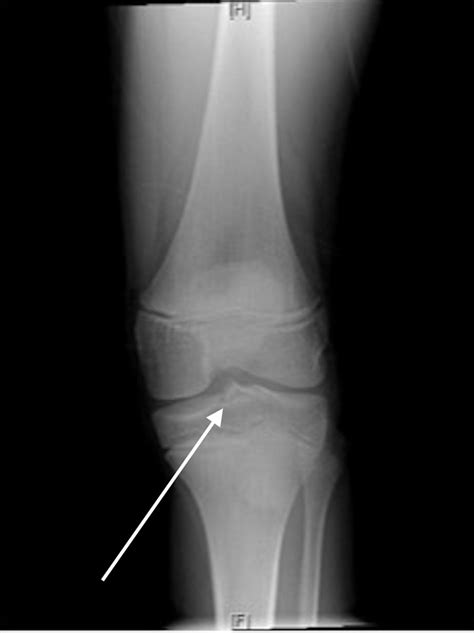

Knee Xray - Century City Los Angeles, CA: Millstein Orthopedics

Knee Xray - Century City Los Angeles, CA: Millstein Orthopedics www.millsteinorthopedics.com

xray arthritic

Traumatic Knee Pain In A Child | The BMJ

Traumatic knee pain in a child | The BMJ www.bmj.com

bmj fracture traumatic